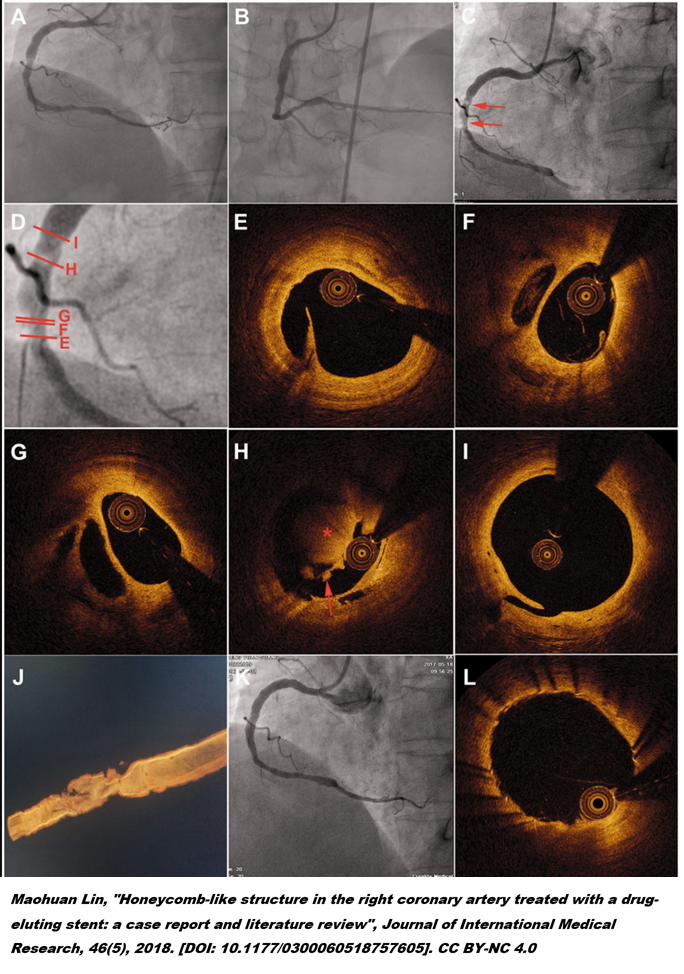

STEMI_PCI.png

13. 그래서 요즘 과학자들은 아직 숙성이 덜 된 비릿한 상태의 경화반을 구분하는 방법에 관심이 많습니다. OCT(혈관 내 촬영, Optical Coherence Tomography) 나 IVUS(혈관 내 초음파 Intravascular Ultrasound)등의 검사는 얇은 섬유막을 가진 취약 경화반을 찾는데 도움이 된다고 알려졌습니다.